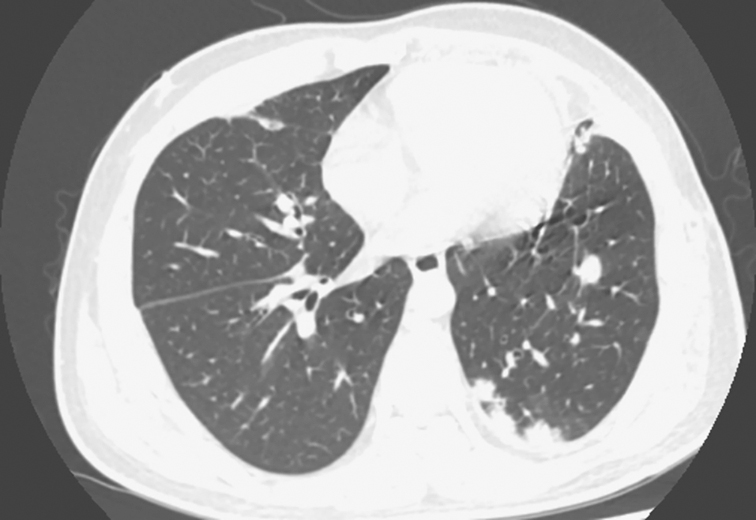

1小时条评论54岁男性,50天前开始咳嗽、咳黄痰,病程后期有发热,双肺可闻湿啰音。影像学可见双肺多发片状密度增高影,伴有空洞形成,且短时间内影像学改变明显,由多发斑片影发展为多发空洞,继而出现局部肺不张及实变。需要做哪些检查以明确病因? 一、入院疑诊 (一...